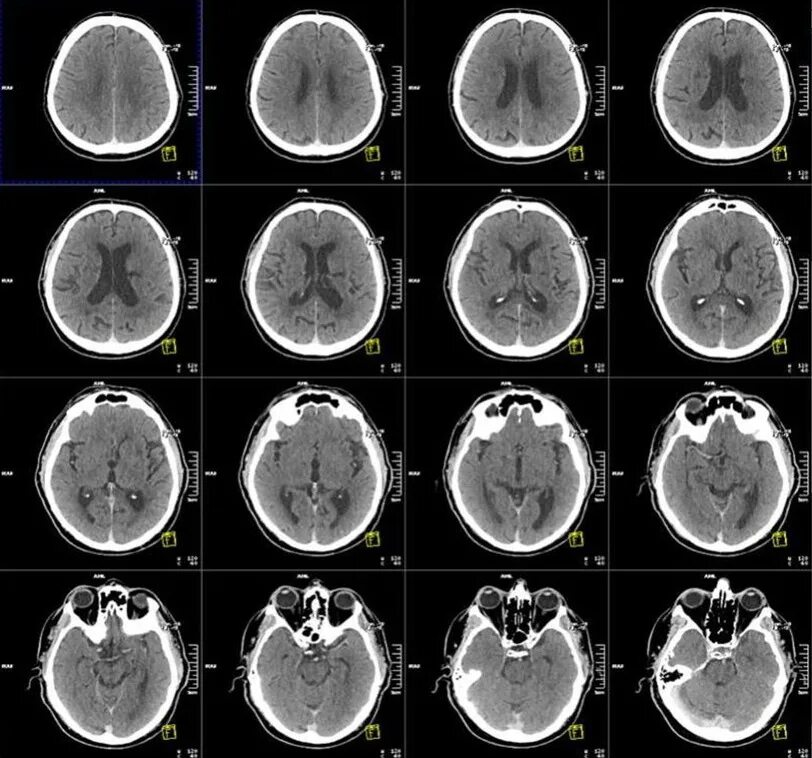

Просмотр снимков мрт